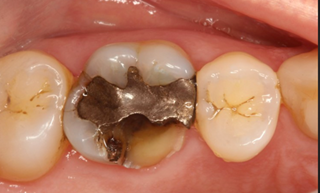

3. Loose or Damaged Filling

Fillings are not permanent and can wear down or break over time. When this happens, the underlying tooth may become exposed and sensitive to pressure.

Old fillings can crack or loosen over time, exposing sensitive areas.

Signs:

- Pain when biting

- Food getting stuck

- Rough or uneven tooth surface

Treatment:

- Replace filling

- Upgrade to crown if needed